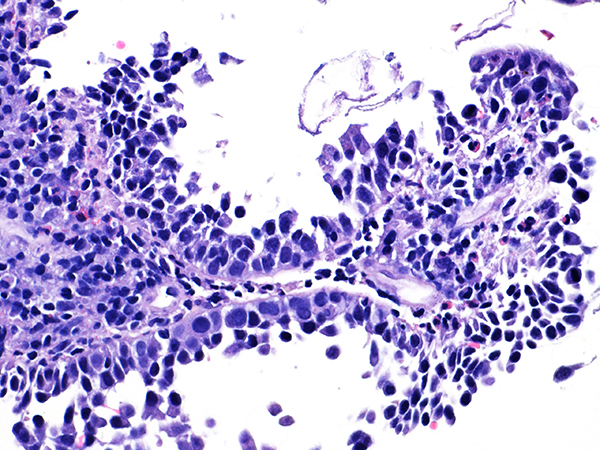

Case 3

Soft Bx CIN 2-3 10x - Low Power

![]() Case 3

Soft Bx CIN 3

10x - Low Power |